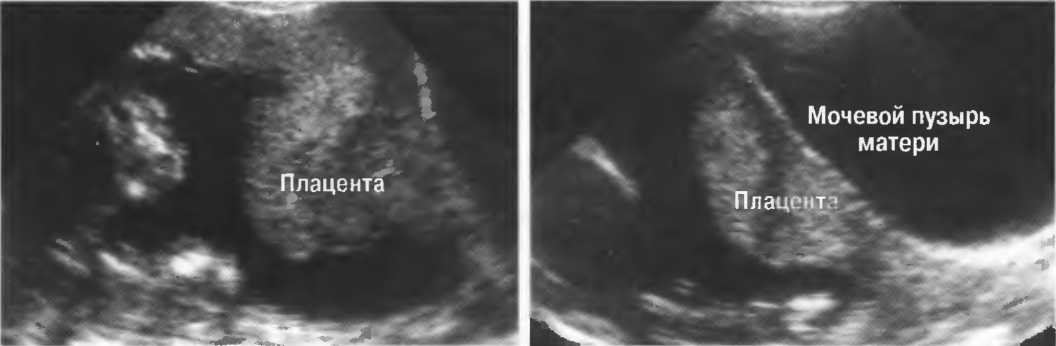

Подготовка

1. Подготовка